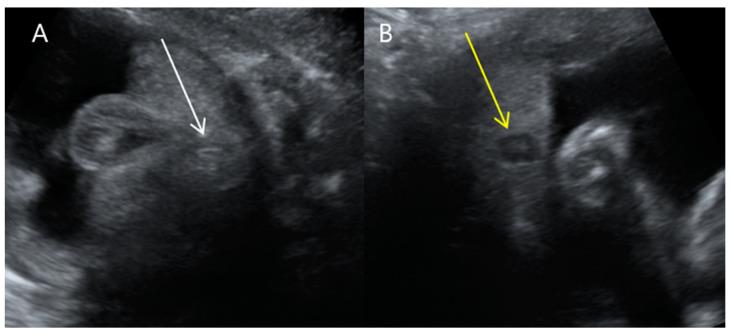

: VACTERL association is a widely known congenital malformation that includes vertebral, anal, cardiac, tracheoesophageal, renal, and limb anomalies. Patients with VACTERL and hydrocephalus appear to form a distinct group, both genetically and phenotypically, and their condition has been called VACTERL-H syndrome. Most cases of VACTERL-H have been reported postnatally, as VACTER-H syndrome is difficult to diagnose prenatally. Here, we report a case of VACTERL-H syndrome in a dichorionic and diamniotic twin diagnosed prenatally by ultrasonography and confirmed postnatally by three-dimensional computed tomography (3D CT). A 34-year-old multiparous female was referred to our institution at 31 + 3 weeks gestation for suspected fetal ventriculomegaly. Detailed examinations using two-dimensional and Doppler ultrasounds revealed hydrocephalus, bilateral dysplastic upper arms, radial aplasia, unilateral pulmonary agenesis, dextrocardia with right atrial enlargement, a unilateral hypoplastic ectopic kidney, a single umbilical artery, a tracheoesophageal fistula with a small stomach, polyhydramnios, and anal atresia. Findings from the postnatal 3D CT aligned with the prenatal diagnosis, showing upper-limb agenesis, dextrocardia with pulmonary hypoplasia, tracheoesophageal fistula, imperforate anus, and colon dilatation. The affected 1390-g male twin had an unaffected 1890-g female twin sister and a healthy 6-year-old brother. : Upon encountering fetuses with multiple anomalies, including ventriculomegaly, a small stomach with polyhydramnios, an abnormally positioned heart, and upper-limb abnormalities, clinicians should perform systematic ultrasonographic examinations to detect associated anomalies and be aware of VACTERL-H syndrome.

VACTERL 协会是一种广为人知的先天性畸形,包括脊柱、肛门、心脏、气管食管、肾脏和肢体异常。患有 VACTERL 和脑积水的患者似乎在遗传和表型上形成了一个独特的群体,他们的病情被称为 VACTERL-H 综合征。大多数 VACTERL-H 病例都是在产后报告的,因为 VACTERL-H 综合征很难在产前诊断。在这里,我们报告了一例产前通过超声诊断并通过三维 CT 产后证实的双绒毛膜和双羊膜性双胞胎 VACTERL-H 综合征病例。一位 34 岁的多产妇在 31+3 周妊娠时因疑似胎儿脑室扩大被转诊至我们机构。使用二维和多普勒超声进行的详细检查显示脑积水、双侧发育不良的上臂、桡骨发育不全、单侧肺发育不全、右心房扩大的右位心、单侧发育不良的异位肾、单脐动脉、伴有小胃的气管食管瘘、羊水过多和肛门闭锁。产后的 3D CT 检查结果与产前诊断一致,显示上肢发育不全、肺发育不全的右位心、气管食管瘘、肛门闭锁和结肠扩张。受影响的 1390 克男性双胞胎有一个未受影响的 1890 克女性双胞胎妹妹和一个健康的 6 岁弟弟。